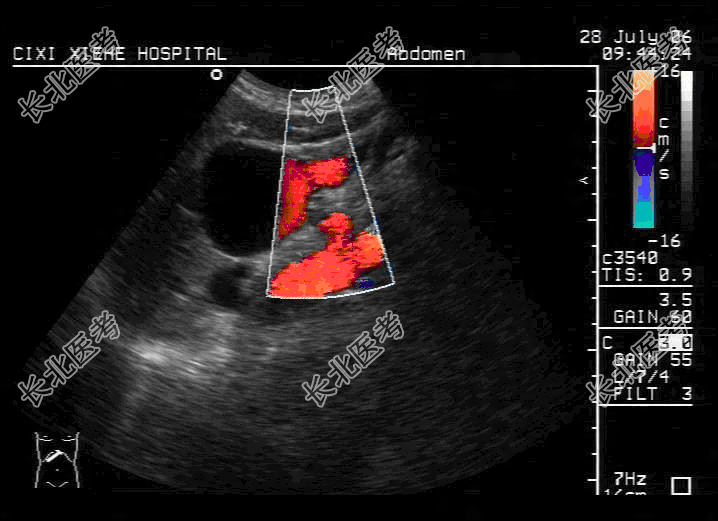

- 单项选择题女,82岁, 右乳癌根治术后5个月来我院化疗。入院后各项化验结果均正常范围,行超声检查时发现第一肝门部见50cm×43cm囊性包块, 边界清,其内透声可, 余肝内未见明显异常回声,未见肝内、外胆管扩张。胆囊、胰腺未见明显异常。超声声像图如图, 应诊断为

A、门静脉瘤

B、先天性胆总管囊状扩张

C、肝囊肿

D、小网膜囊肿

E、以上都不是